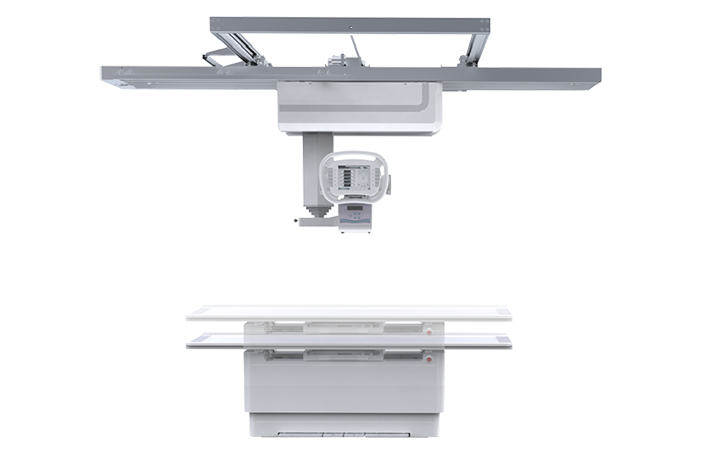

● 自动对中

球管自动对准探测器中心点,保证画面成像视野准确,无需医生手动校准。

● 自动跟踪

配备球管与平板联动控制系统,平板端上下移动时,球管端自动跟踪。

● 拍摄无死角

悬吊运动范围大,牛头可全角度旋转,倾斜投照位可满足特殊病人的临床应用。

● 球管运动灵活

球管上下升降范围大,便于站立位时足踝负重状态下的检查。